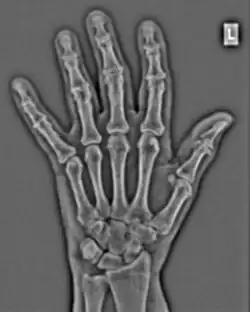

The conventional way of interpreting radiographic images in medicine is to regard them as representations of human anatomy. In the mathematical analysis of these images, however, we can interpret them as fluctuations of signal amplitude in space, as demonstrated in Figure 1.23.

FFTs can also be calculated in two-dimensions to give results such as those in Figure 1.27. Since Fourier analysis generates results in terms of both positive and negative spatial frequencies, these can be plotted in the form of a 2D image so that the maximum frequency lies at the origin and those for the horizontal and vertical directions are shown increasing towards that origin. The modulation at different spatial frequencies is represented using a grey-scale. Low frequency bands can be seen along the horizontal axis in the figure, for example, representing the horizontal periodicity of image data from the fingers, while finer bands along the y-dimension are indicative of a periodicity of image data from the various metacarpophalangeal joints. Higher frequency features can also be seen running diagonally in this 2D-FFT, representative of the trabecular structure of the bones, for example.

The essence of this approach is that it can be used to produce a range of image processing effects by enhancing and/or suppressing features in the 2D-FFT and then converting the result back into the spatial domain using the IFT, as illustrated in Figure 1.28. Such image manipulations are considered in more detail in a later chapter. Note that the form of image processing demonstrated in the figure is for purely illustrative purposes and bears no direct medical significance.